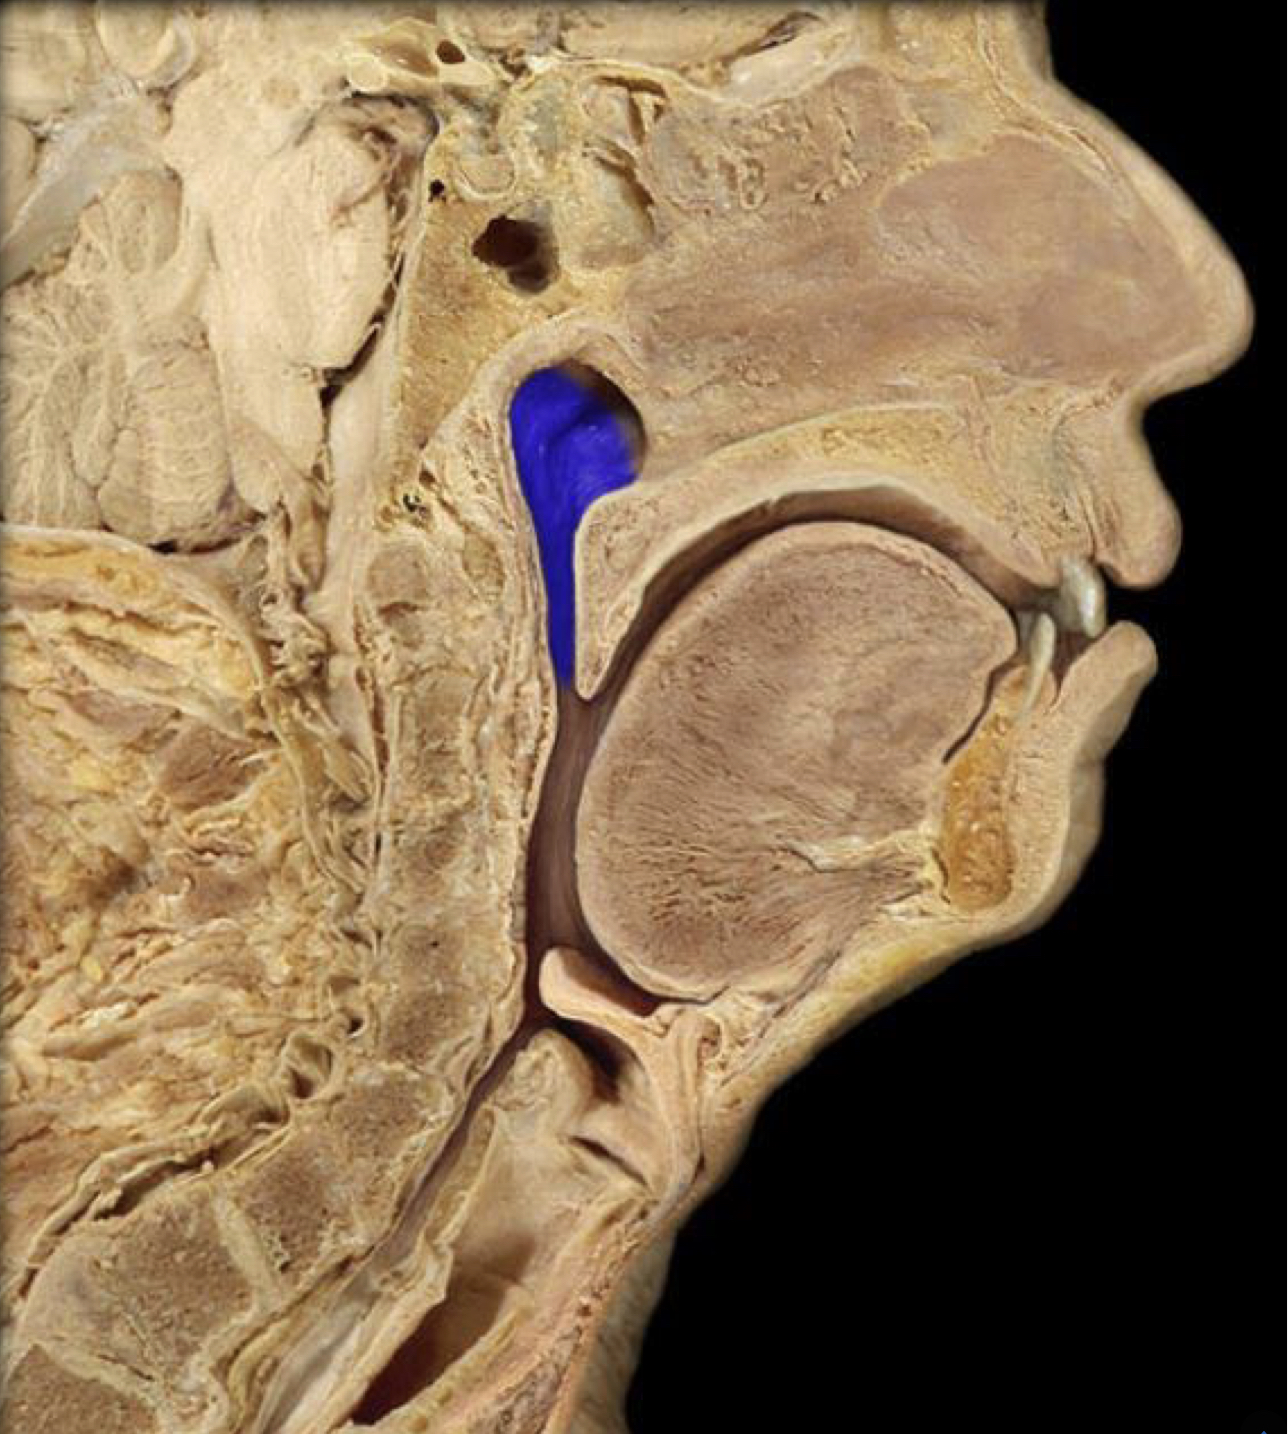

What structure is highlighted in blue?

Oropharynx